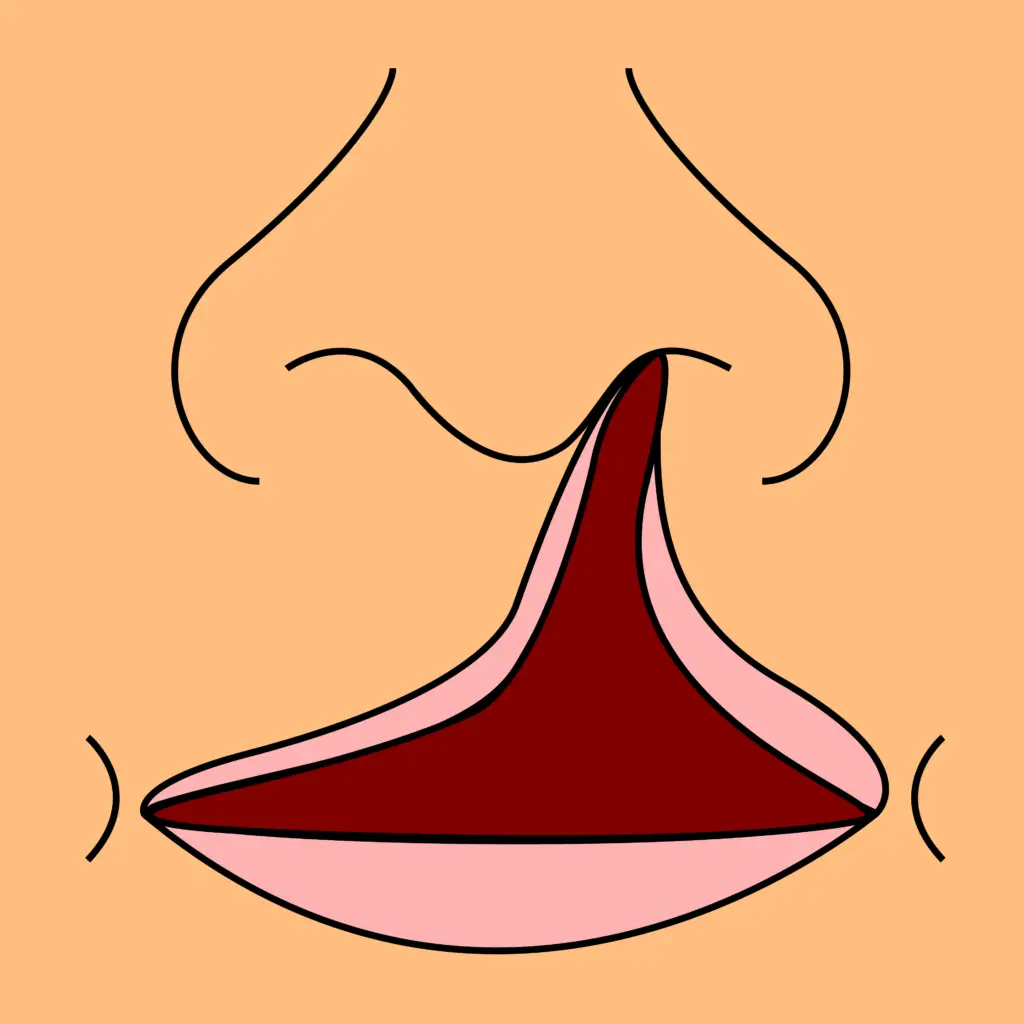

Cleft Lip and Palate

Comprehensive surgical correction of cleft lip and palate for improved speech, feeding, and facial harmony. Procedures are planned meticulously for long-term functional and aesthetic success. Multidisciplinary care ensures holistic outcomes.